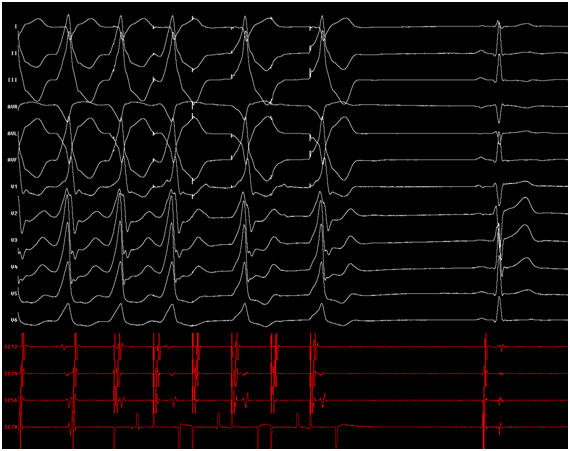

Certainly, the patient presented a regular, wide QRS complex tachycardia, with right bundle branch block morphology in precordial leads, inferior axis and positive precordial concordance (Figure 1). During the electrophysiological study, a decapolar catheter was placed in the coronary sinus, a quadripolar catheter in His, and another in a right ventricle tip. The baseline conduction times were within normal limits. During oversensing extra stimulation and with programmed atrial stimulation with decreasing cycles, progressive widening of the QRS complex was observed with left bundle branch block morphology but with a negative QRS complex in aVL and prolongation of the HV interval up to 84 msec. With even shorter cycles, the QRS complex morphology changed to right bundle branch block with greater prolongation of the HV interval up to 94 msec (Figure 2). With programmed atrial stimulation in the proximal coronary sinus, we observed a dual AV nodal pathway physiology with a single narrow echo beats. With shorter cycles and longer AV prolongation, clinical tachycardia was induced (Figure 3). This tachycardia presented an atrio-ventricular ratio of 1 to 1 with concentric retroconduction and variable VA intervals (mostly short).

Figure 3 (A) Programmed atrial stimulation: AV jump and AV reentry with a narrow QRS complex. (B) In shorter cycles, narrow QRS complex tachycardia.